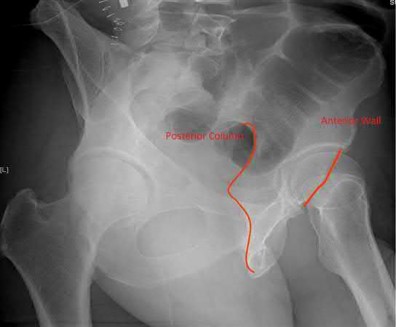

Question 22:

During an ilioinguinal approach to the acetabulum, massive bleeding occurs while dissecting over the superior pubic ramus near the symphysis. The injured vessel, commonly referred to as the 'corona mortis,' typically represents an anastomosis between the obturator artery and which of the following?

Explanation:

The 'corona mortis' (crown of death) is an anatomical variant describing an anastomosis between the obturator system and the external iliac or inferior epigastric system. It is located on the posterior aspect of the superior pubic ramus. Injury to this vessel during pelvic or acetabular surgery (like the ilioinguinal or Stoppa approaches) can lead to severe, difficult-to-control hemorrhage.